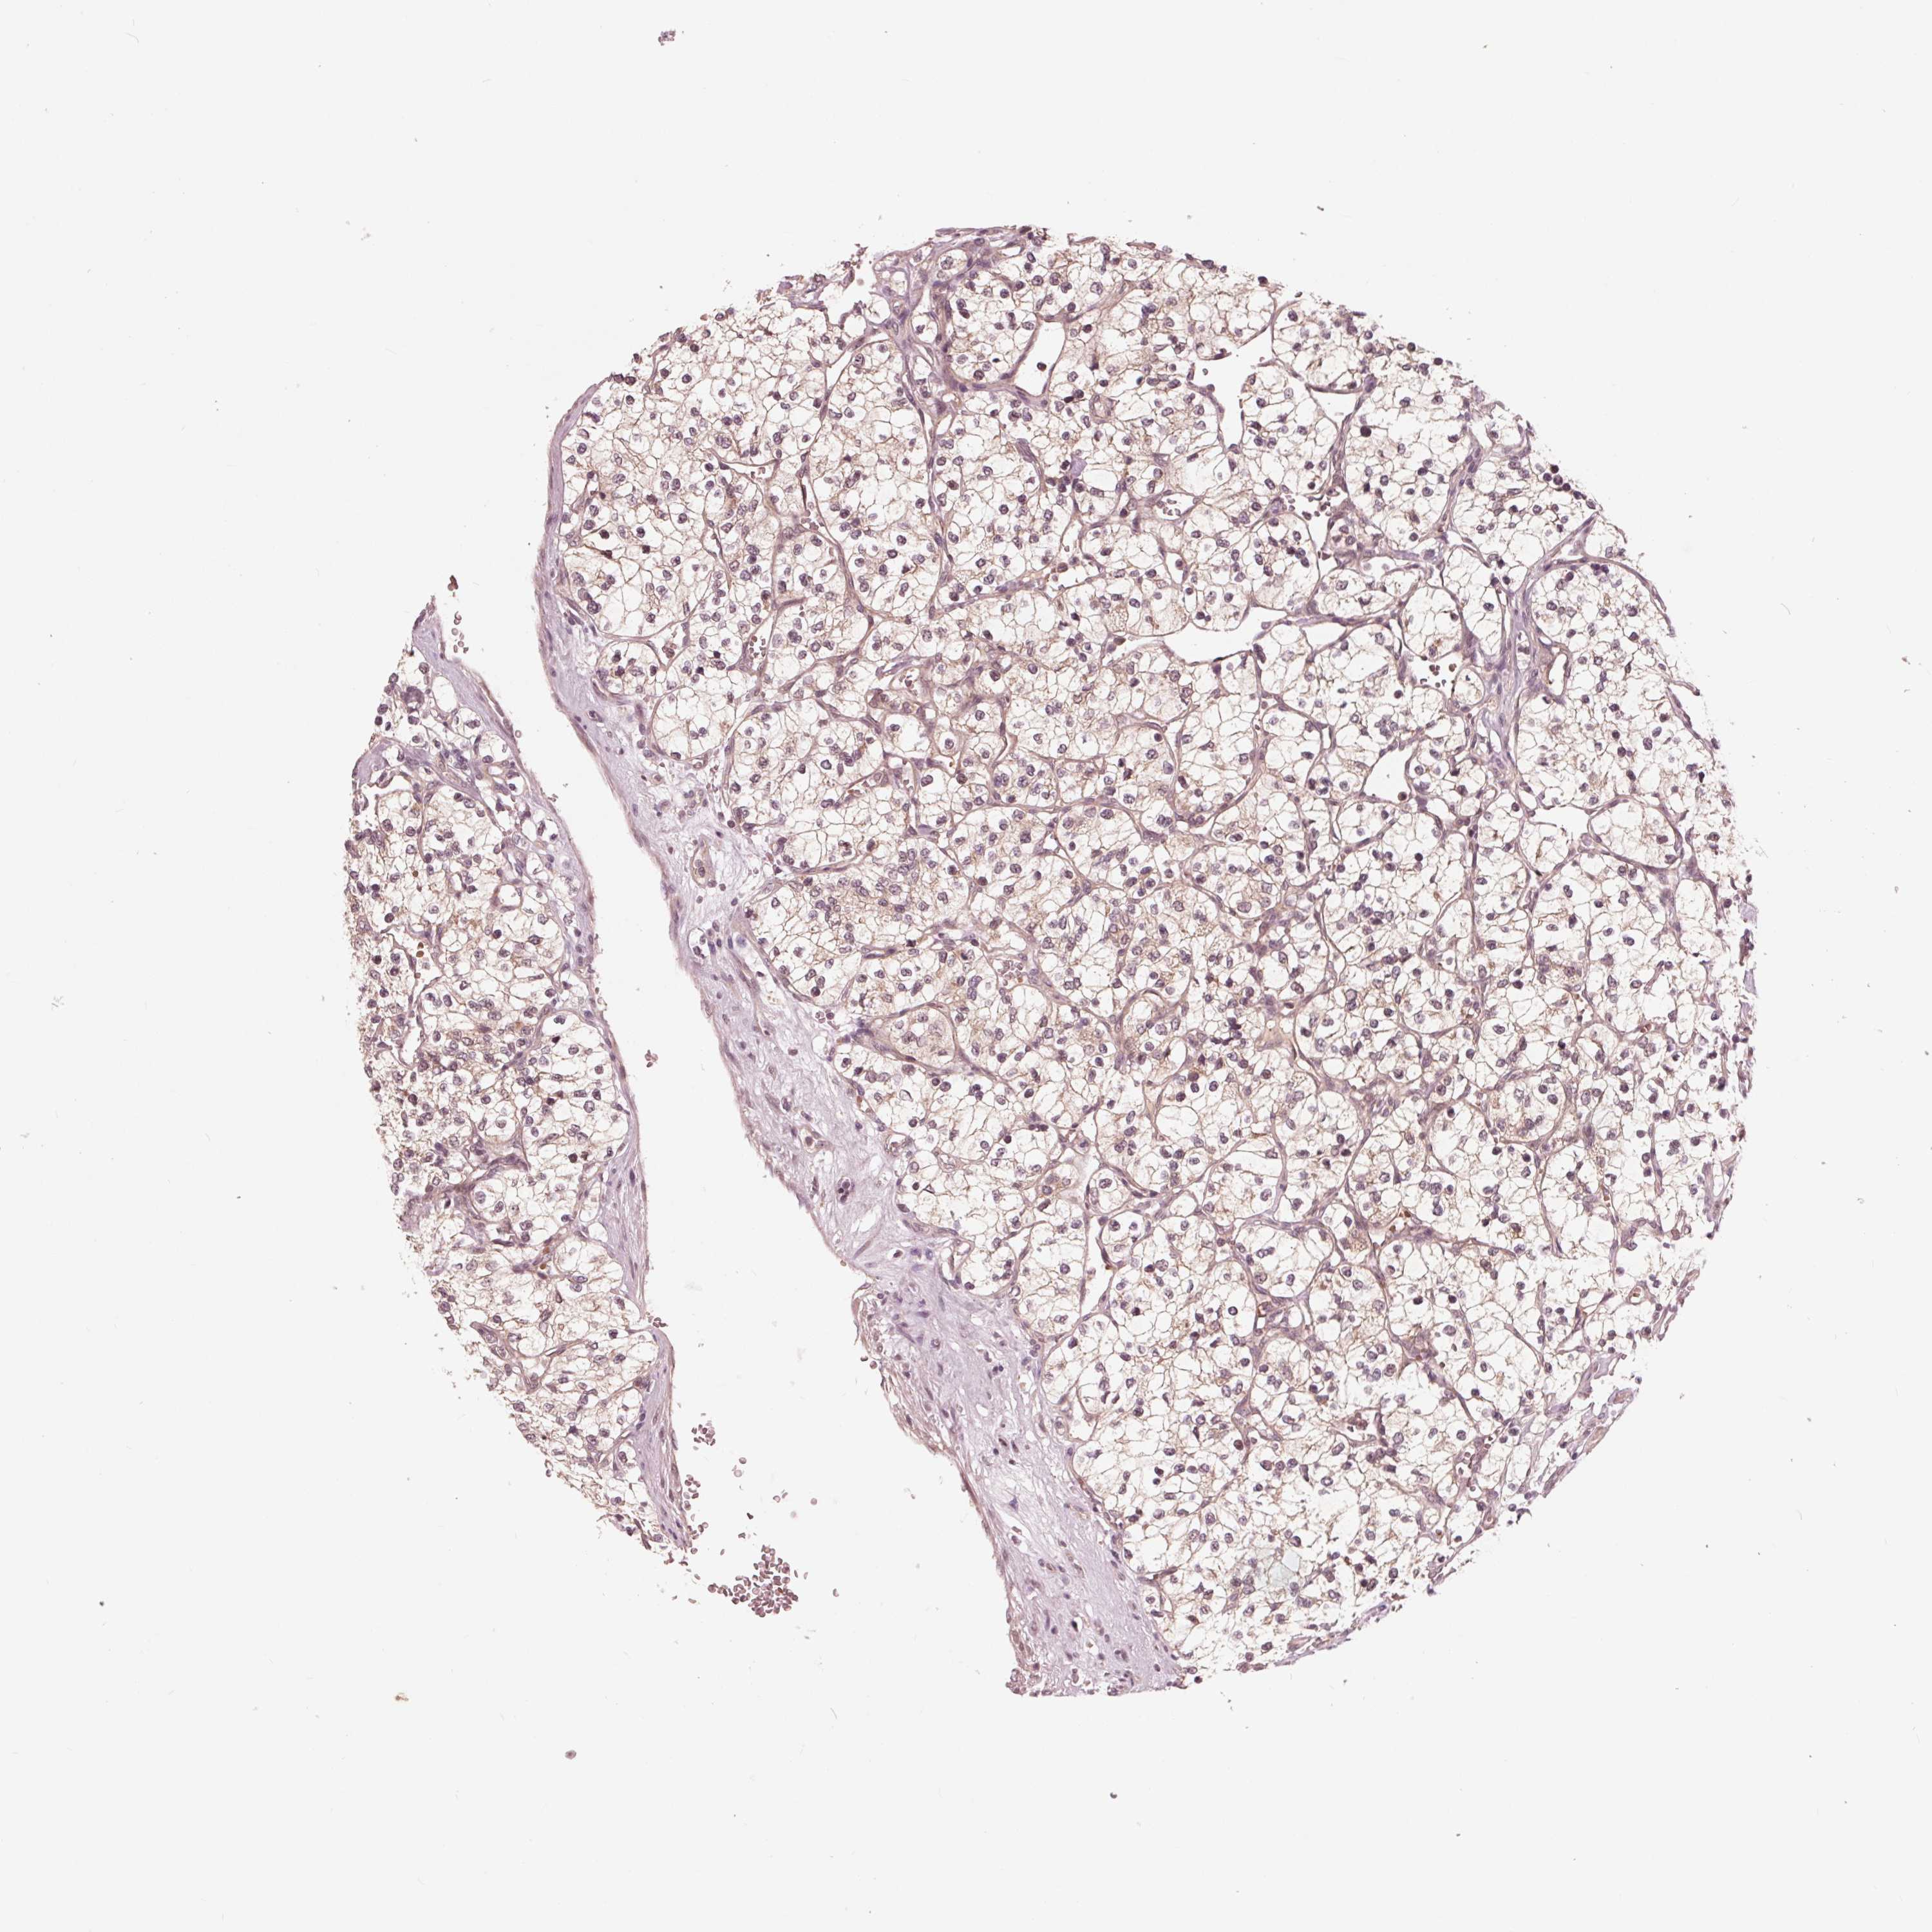

KIDNEY RENAL CLEAR CELL CARCINOMA (VALIDATION) - Interactive survival scatter ploti

The Survival Scatter plot shows the clinical status (i.e. dead or alive) for all individuals in the patient cohort, based on the same data that underlies the corresponding Kaplan-Meier plots. Patients that are alive at last time for follow-up are shown in blue and patients who have died during the study are shown in red.

The x-axis shows the expression levels (FPKM) of the investigated gene in the tumor tissue at the time of diagnosis. The y-axis shows the follow-up time after diagnosis (years). Both axes are complimented with kernel density curves demonstrating the data density over the axes. The top density plot shows the expression levels (FPKM) distribution among dead (red) and alive patients (blue). The right density plot shows the data density of the survived years of dead patients with high and low expression levels respectively, stratified using the cutoff indicated by the vertical dashed line through the Survival Scatter plot. This cutoff is automatically defined based on the FPKM cutoff that minimizes the p-score. The cutoff can be changed by dragging the vertical line or by entering a cutoff value in the square labeled "Current cut-off".

Under the Survival Scatter plot the p-score landscape (black curve; left axis) is shown together with dead median separation (red curve; right axis). Dead median separation is the difference in median mRNA expression between patients who have died with high and low expression, respectively. It is calculated as follows: median FPKM expression of dead patients with high expression - median FPKM expression of dead patients with low expression. This is intended to aid the user in visually exploring custom cutoffs and the associated p-scores and dead median separation.

& Survival analysisi

Kaplan-Meier plots summarize results from analysis of correlation between mRNA expression level and patient survival. Patients were divided based on level of expression into one of the two groups "low" (under cut off) or "high" (over cut off). X-axis shows time for survival (years) and y-axis shows the probability of survival, where 1.0 corresponds to 100 percent.

UBALD1 is not prognostic in Kidney Renal Clear Cell Carcinoma (validation)

: 21.42

Average pTPM 21.8

Number of samples 100